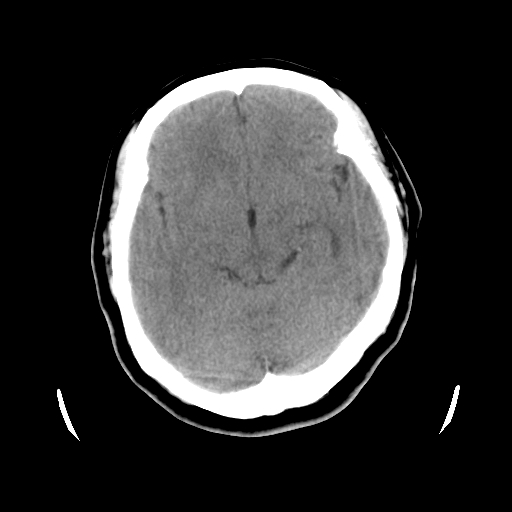

以下是引用cgf在2010-1-3 17:53:00的发言:[br]此病例多考虑:透明隔发育异常 透明隔囊肿可能性大;右侧基底节区(尾状核头)小片状低密度影考虑陈旧性腔梗[br][br]透明隔发育异常:包括透明隔间腔(第五脑室)、韦氏腔(第六脑室)、透明隔囊肿、透明隔缺如;前两者属于正常变异,后两者属于发育畸形;[br]透明隔间腔向下扩张形成韦氏腔;[br]有时透明隔间腔与透明隔囊肿很难鉴别;透明隔间腔间距一般不超过0.5cm,间距大于0.5cm时应考虑透明隔囊肿;[br]透明隔缺如为两侧脑室间隔缺如、融合成单脑室畸形,可伴有智力发育异常;[br][br]

以下是引用liaoqiang在2010-1-3 16:04:00的发言:[br]考虑侧脑室脉络丛囊肿?不除外变异的威氏腔。

以下是引用江广1996在2010-1-3 20:17:00的发言:[br]考虑变异的威氏腔。不除外侧脑室脉络丛囊肿.[br]透明隔囊肿大多数偏前,在侧脑室前角之间。